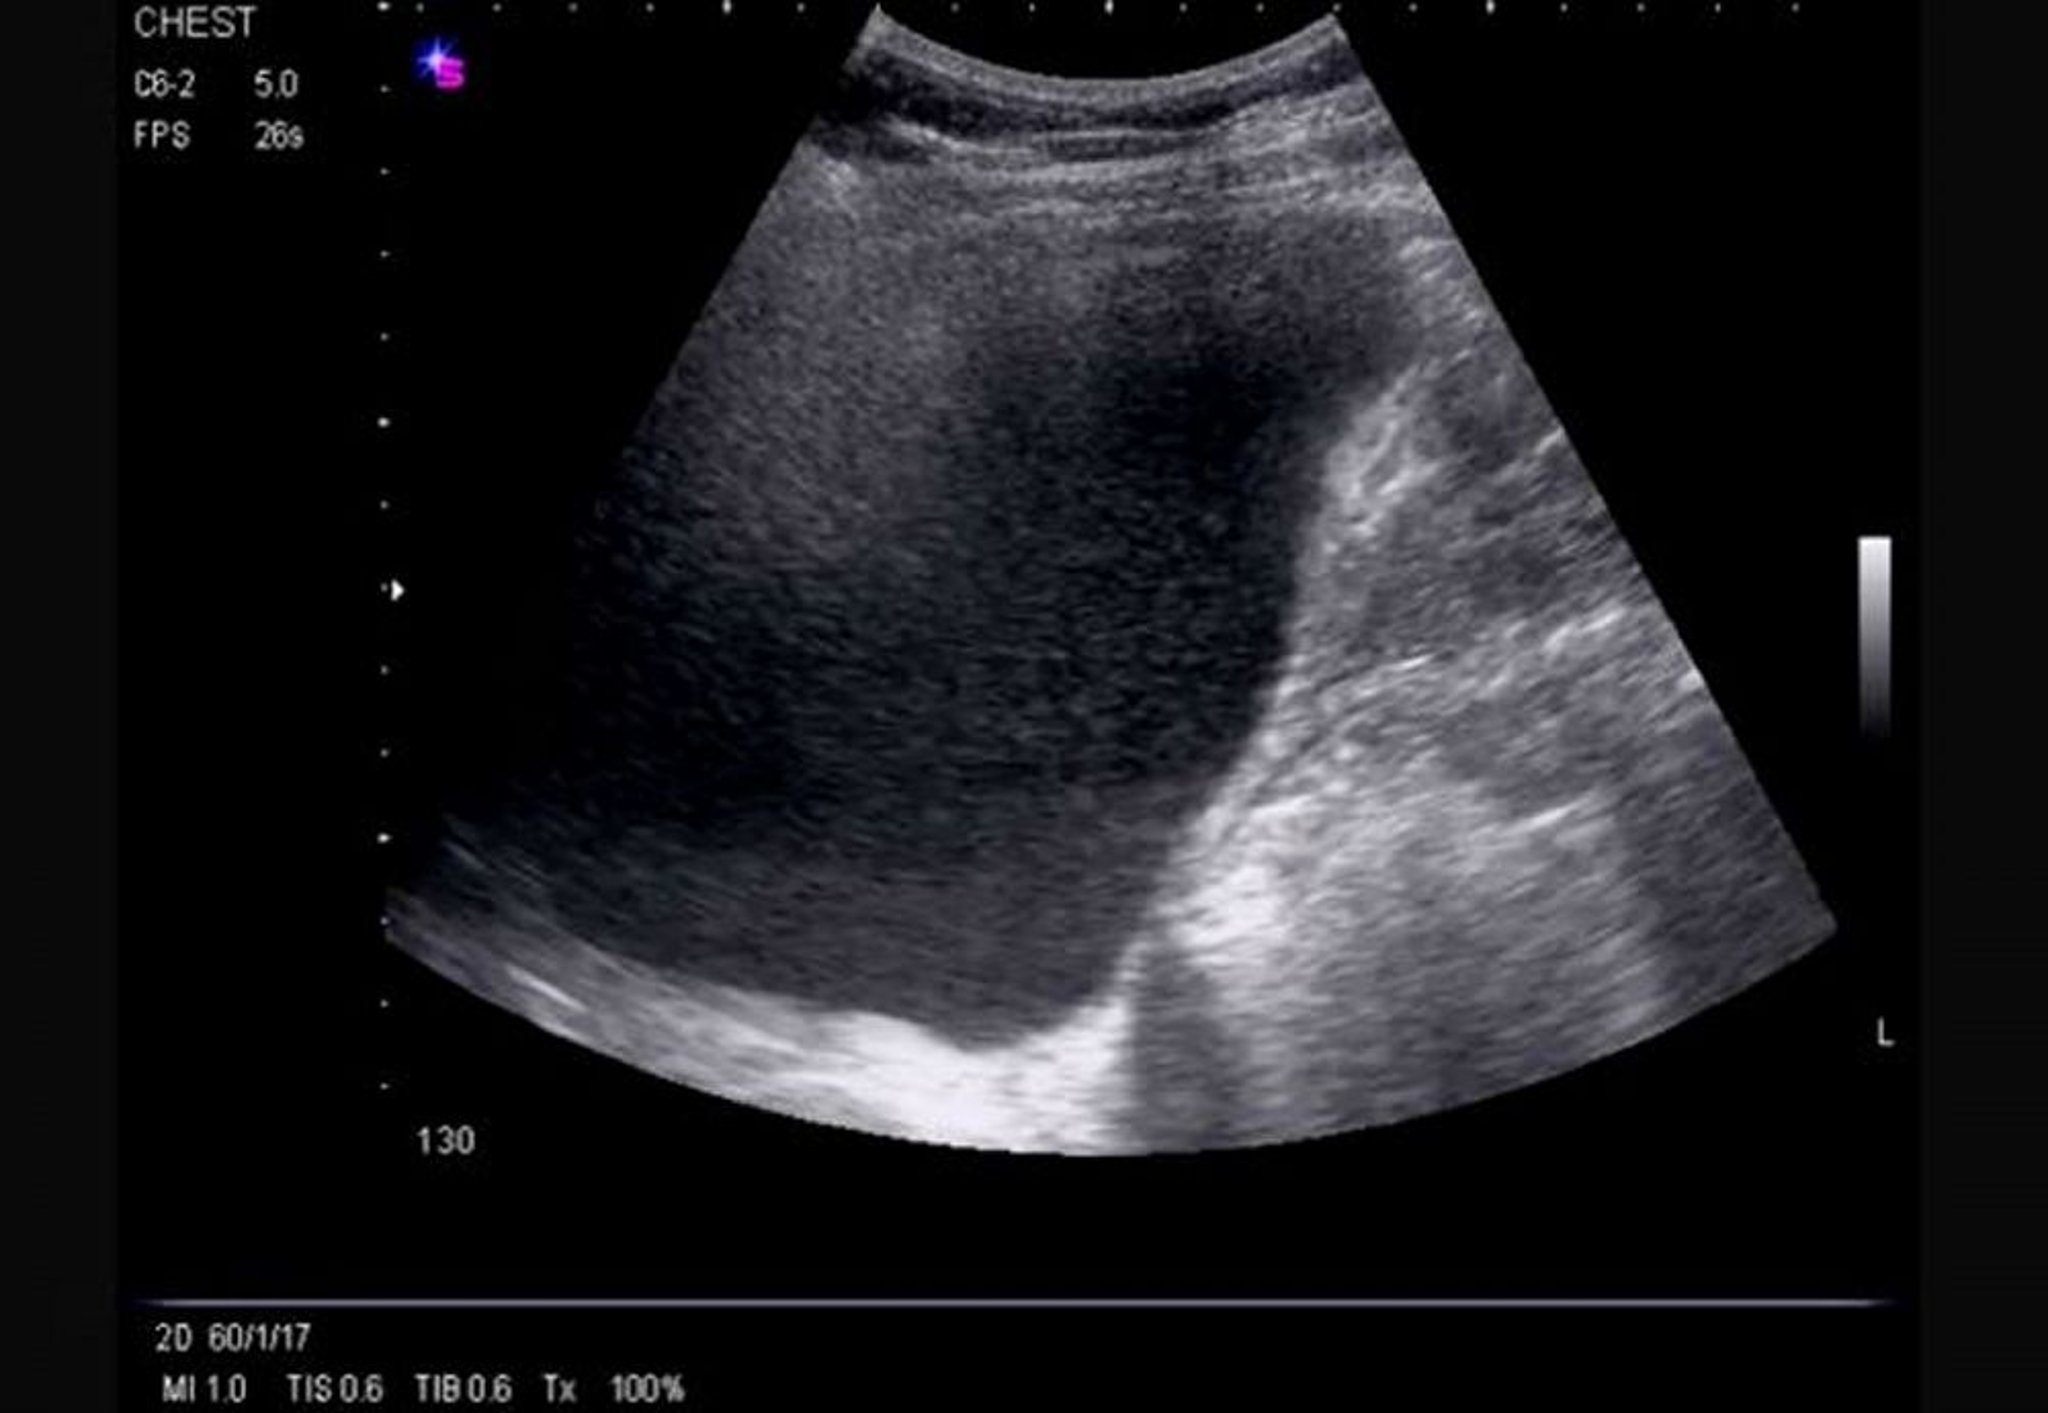

胸部外側の超音波検査(右)

この超音波画像では,流動性のある大量の右側胸水により片側横隔膜の反転が生じており,胸水はエコー源性を示している。

Image courtesy of Najib M.Rahman, BMBCh MA (oxon) DPhil.